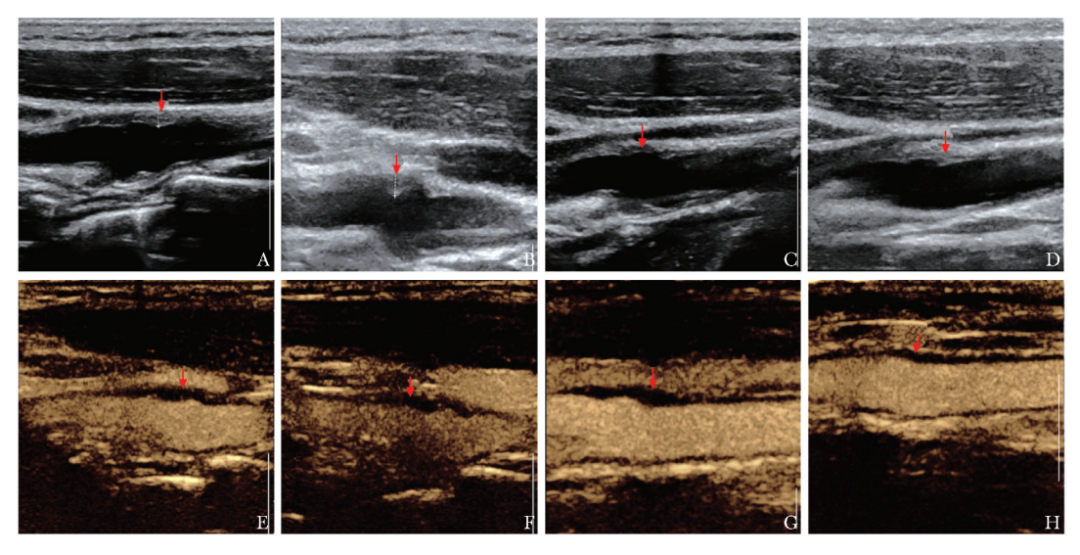

左证关系查验,长入患者病史,临床概述计划为血管壁炎。现在,患者已剿袭调理约7个月。调理1个月时,患者左颈部难受彰着改善,调理3个月时颈部不适症状缓解,压痛隐没。在动态随诊进程中,患者进行了血老例、hs-CRP、生化及肿瘤秀雅物等查验,限度均未见彰着特殊。在调理1个月、3个月、5个月、7个月期间别进行颈动脉CEUS查验,随访各时期点颈动脉病变处管壁周围低回声浸润情况、累及规模、CEUS增强进度及炎症消退情况。调理1个月、3个月、5个月及7个月后随访的灰阶超声图像袒露,病变管壁周围增厚的低回声厚度冉冉变薄,从初次复查的0.23cm减少至最近一次复查的0.16cm;同期,累及长度由初次复查的2.6cm冉冉减小至2.1cm,且病变回声冉冉增强(图3A~3D)。调理1个月、3个月、5个月及7个月后随访的CEUS图像袒露,增厚低回声内可见不同进度的微泡填充,从初次复查的中度增强冉冉减轻至最近一次的轻度增强,进度较前彰着减低(图3E~3H)。

图3患者调理后随诊老例灰阶超声及超声造影查验限度(箭头)

A~D.别离为调理1个月、3个月、5个月及7个月后随访的灰阶超声图像;E~H.别离为调理1个月、3个月、5个月及7个月后随访的超声造影图像